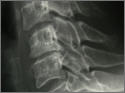

Halswirbelsäule

Die neue OP-Methode in Bildern

Schonende OP-Methode: Als neueste Operationsmethode an der Halswirbelsäule steht uns nun mehr als Ersatz einer abgenützten Bandscheibe die künstliche Bandscheibenprothese zur Verfügung. Sie erhält die Beweglichkeit der Halswirbelsäule auch nach der Operation.